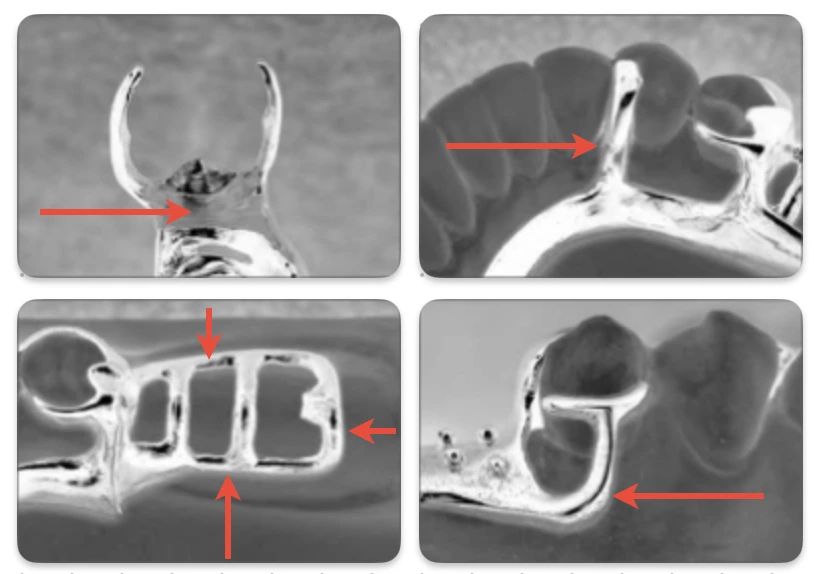

• These minor connectors can be described in three groups. An open latticework or ladder type of design is preferable and is conveniently made by using preformed 12-gauge half-round and 18-gauge round wax strips.

1. Open construction

2. Mesh construction

3. Bead, wire or nailhead components on a metal base.

Open construction

• Consists of longitudinal and transverse struts that form a ladder-like network.

• Provides the strongest attachment of acrylic resin to the denture framework, and can be used whenever multiple teeth are to be replaced.

• Also facilitates relining and rebasing of removable partial dentures.

• Longitudinal strut

• Mandibular arch : One should be positioned buccal to the crest of the ridge and the other lingual to the crest.

• Maxillary arch : One should be positioned buccal to the ridge crest, while the border of the major connector generally acts as the second longitudinal strut.

• Transverse strut : Ideally it should be designed to pass between the necks of the artificial teeth.

• The longitudinal and transverse struts should be encircled by the acrylic resin to provide retention to the denture base. This can be achieved by providing suitable relief using wax (24-26 gauge) to the areas of master cast (that are to feature open construction) during framework fabrication process.

Mesh construction

• May be compared to a rigid metallic screen, with channels that pass through the connector.

• The channels are intended to permit acrylic resin penetration, which allows encirclement of the minor connector with the resin and mechanical retention of the denture base.

• Relief and border extension is similar to open construction.

• Drawback :

• Difficulty in packing of acrylic resin: Increased pressure is needed to force resin through the small holes in the minor connector. Insufficient packing pressure may result in inadequate resin penetration and a weak attachment to the framework.

• Mesh must cover the entire ridge crest and cannot be limited to those areas between the necks of prosthetic teeth. Hence, it may interfere with the arrangement of prosthetic teeth.

Bead, nailhead, or wire construction

• Often used in conjunction with metal denture bases, where in the metal bases are cast to fit directly against the underlying soft tissues, and resin is attached to the free surface of such bases.

• Retention is gained by encompassment of surface projections.

• No relief is provided beneath these minor connectors, as the metal bases are in direct contact with the underlying tissue.

• Fabrication : Beads and nailheads may be created by placing resin beads on the appropriate segments of the wax pattern, while, wire construction involves casting or soldering of irregular wire forms to a metal base.